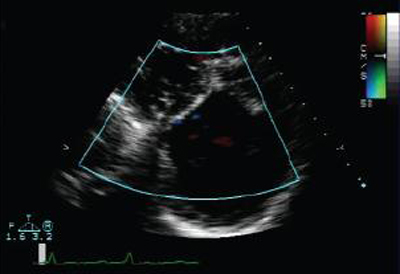

Short axis echocardiographic view in a patient with pulmonary regurgitation following repair of tetralogy of Fallot. The patient has a restrictive right ventricle, and short axis echocardiographic view reveals a small right ventricle

From: Chaturvedi RR, Redington AN. Heart. 2007 Jul;93(7):880-9; used with permission